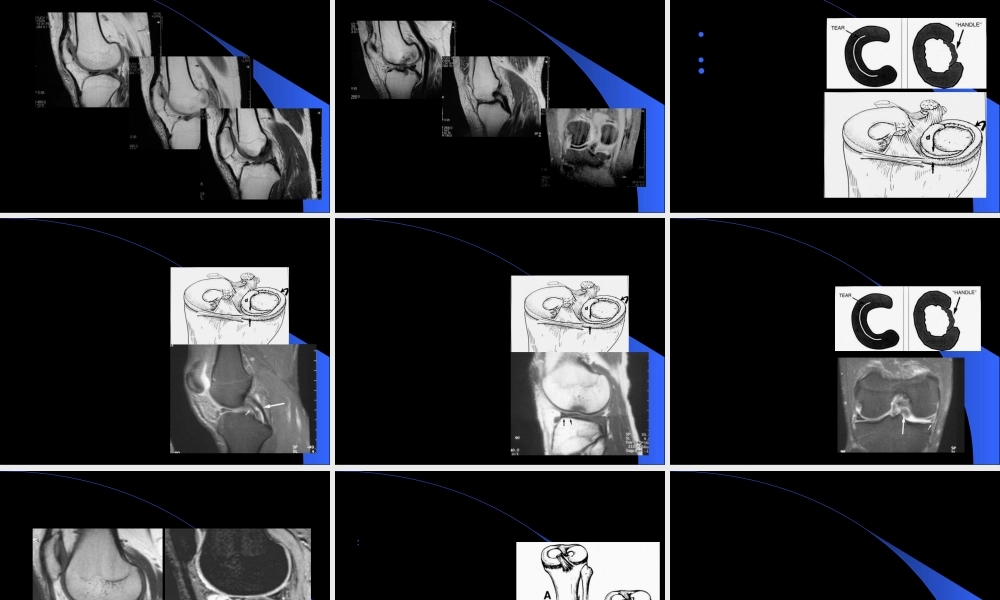

MRIMRI在膝关节创伤在膝关节创伤(chuāngshāng)(chuāngshāng)的应用的应用第一页,共五十一页。膝关节创伤的MRI半月板病变(bìngbiàn)韧带病变软骨病变其它第二页,共五十一页。半月板-解剖纤维软骨结构LM:类圆形(O),前后部分相对等宽–外周疏松连接,外后腘肌腱和鞘与关节囊分开–半月板股骨韧带MM:半圆形(C),后部(hòubù)比前部宽–外周与关节囊紧密连接10MM3LM2ACL8PCL第三页,共五十一页。半月板-技术考虑矢状位和冠状位短TE图像(túxiànɡ)优于长TE图像(túxiànɡ)-T1WI,PDWI,GRE优于T2WI第四页,共五十一页。正常半月板断层表现第五页,共五十一页。半月板撕裂诊断标准信号异常:Grade0:纤维软骨结构,所有(suǒyǒu)序列上低信号Grade2:变性Grade3:半月板撕裂第六页,共五十一页。半月板撕裂-Grade3信号第七页,共五十一页。半月板-Grade2信号可以演变(yǎnbiàn)为撕裂第八页,共五十一页。半月板撕裂-形态异常游离(yóulí)缘变钝小的三角形破碎消失领结中断局限性凹陷后角小于前角外侧半月板前角高度>6mm第九页,共五十一页。半月板撕裂诊断标准同时(tóngshí)考虑信号和形态的改变第十页,共五十一页。半月板特殊信号异常半月板内撕裂(sīliè)或囊肿第十一页,共五十一页。半月板撕裂分类层裂斜裂纵裂(zònɡliè)放射状撕裂注:MR的作用在于(zàiyú)明确有无撕裂,对撕裂的分型能力相对较差第十二页,共五十一页。见于(jiànyú)外侧半月板后角第十三页,共五十一页。半月板撕裂误诊可能-横韧带第十四页,共五十一页。第十五页,共五十一页。桶炳状撕裂-BHT的定义纵向垂直撕裂(sīliè)或斜行撕裂(sīliè)时合并半月板碎块向关节中央区移位,形如桶柄状内侧多于外侧内移的碎块多位于髁间和/或关节前部第十六页,共五十一页。BHT征象-双PCL征双后交叉(jiāochā)韧带征第十七页,共五十一页。BHT征象-半月板翻转征半月板翻转征(Flippedmeniscussign):半月板前角高度≥6mm;或“双前角征”—两个前角,而后(érhòu)角变短或消失第十八页,共五十一页。BHT征象-碎块内移征碎块内移征:关节(guānjié)髁间区见条状或团状低信号半月板碎块影第十九页,共五十一页。半月板囊肿多见于LM前角,常和半月板层裂同时(tóngshí)存在第二十页,共五十一页。盘状半月板(Discoidmenisci)LM多见分型Watanabeclassification第二十一页,共五十一页。盘状半月板-...